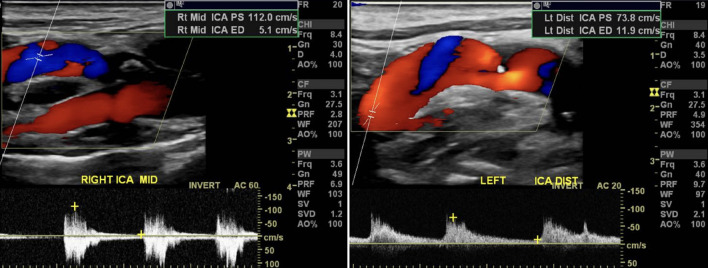

Internal carotid artery webs (ICAWs) have been described as noninflammatory, nonatherosclerotic shelf-like projections of intimal fibrous tissue which may be the culprit for embolic stroke of unknown origin. Carotid webs are an atypical form of intimal fibromuscular dysplasia (FMD) and internal carotid webs create areas of stagnation and recirculation distal to the web that favor thrombus formation and embolism. Symptomatic carotid webs are conventionally associated with young women presenting with few vascular risk factors and < 50% stenosis in the affected ICA. ICAWs are being described more and more in the vascular literature, but the management of this pathology remains unclear. We describe a rare case of a 90-year-old male who presented with a significantly sclerosed symptomatic right ICAW without evidence of comorbid atherosclerotic disease. The clinical management, intraoperative findings, and postoperative course are described herein. At the age of 90, this patient is the oldest case of symptomatic carotid web recorded in the literature. Successful management with a carotid endarterectomy is an appropriate strategy for treatment even in a nonagenarian. We would favor carotid endarterectomy over carotid artery stenting given the circumferential, fibrotic nature of these lesions.